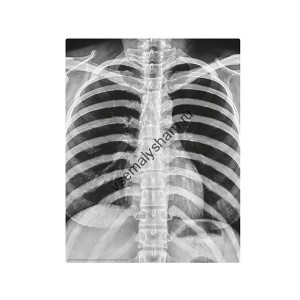

- Код артикула: 00-03375С данным набором ребенок сделает из гипса достоверную модель человеческого скелета. Каждая косточка отливается из гипса отдельно. Затем высохшие детали соединяются вместе по схеме. Собирая скелет, дети лучше всего запоминают его строение и понимают, насколько продуман и интересен человеческий организм.

- Код артикула: 00-03374Набор принесет больше всего пользы, если в сборке моделей будут участвовать родители. Таким образом, удастся преодолеть все сложные моменты и поговорить о строении человека. Необходимую информацию вы найдете в инструкции на русском языке, в которой указаны все этапы работы с набором.